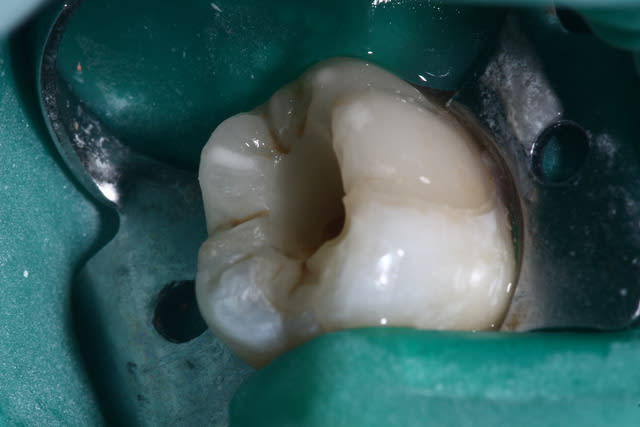

Pour tout ceux qui demandent souvent, si je fais des onlays je vais avoir des nécroses !

ça peut arriver. Cela doit rester exceptionnel si les indications sont bien posées...

Quand ça arrive, et bien on passe a travers comme si la dent était intacte ...

On fait l'endo et on referme avec un compo.

Remarquez que l'onlay explose pas quand on le fraise, ni se décolle quand on le clamp....

C'est pas un problème d'étanchéité au niveau de l'onlay, mais de lésion trop juxta pulpaire.

L'onlay date d'il y a 5 mois...